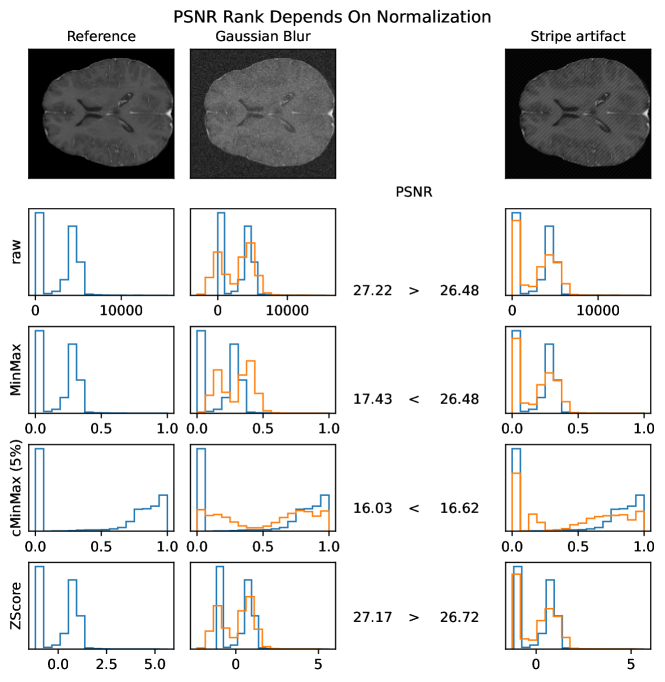

PSNR scores generally display only very small changes for strengths larger than 2 (see Fig. A.1). PSNR values are higher for Zscore normalization.

5 Adverse Examples

In the following, special characteristics of the analyzed metrics, which can be derived from their definition or the experimental results above, are show-cased. We present adverse examples (see Fig. 2-6), where similarity metrics do not perform as intended or expected.

The experiments and adverse examples demonstrate specific strengths and weaknesses of the analyzed metrics. Although SSIM and PSNR are frequently used for the evaluation of synthetic MR images, they are strongly decreased by constant intensity shifts if no normalization is applied. PSNR is very dependent on the kind of normalization, which complicates its use as a comprehensive metric for comparing studies of different authors. SSIM underestimates blurring and thereby favors blurred or additionally blurred images over other distortions.

Some of these observations have already been mentioned by other authors. Similar to SSIM, MSE and MAE were reported to create blurry images [62]. And PSNR and MSE were mentioned to be sensitive to the normalization method [33].